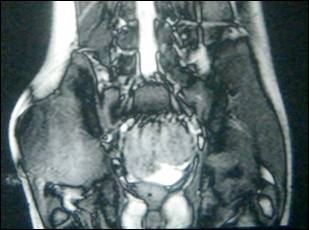

Figure 1: MRI of right gluteal region.